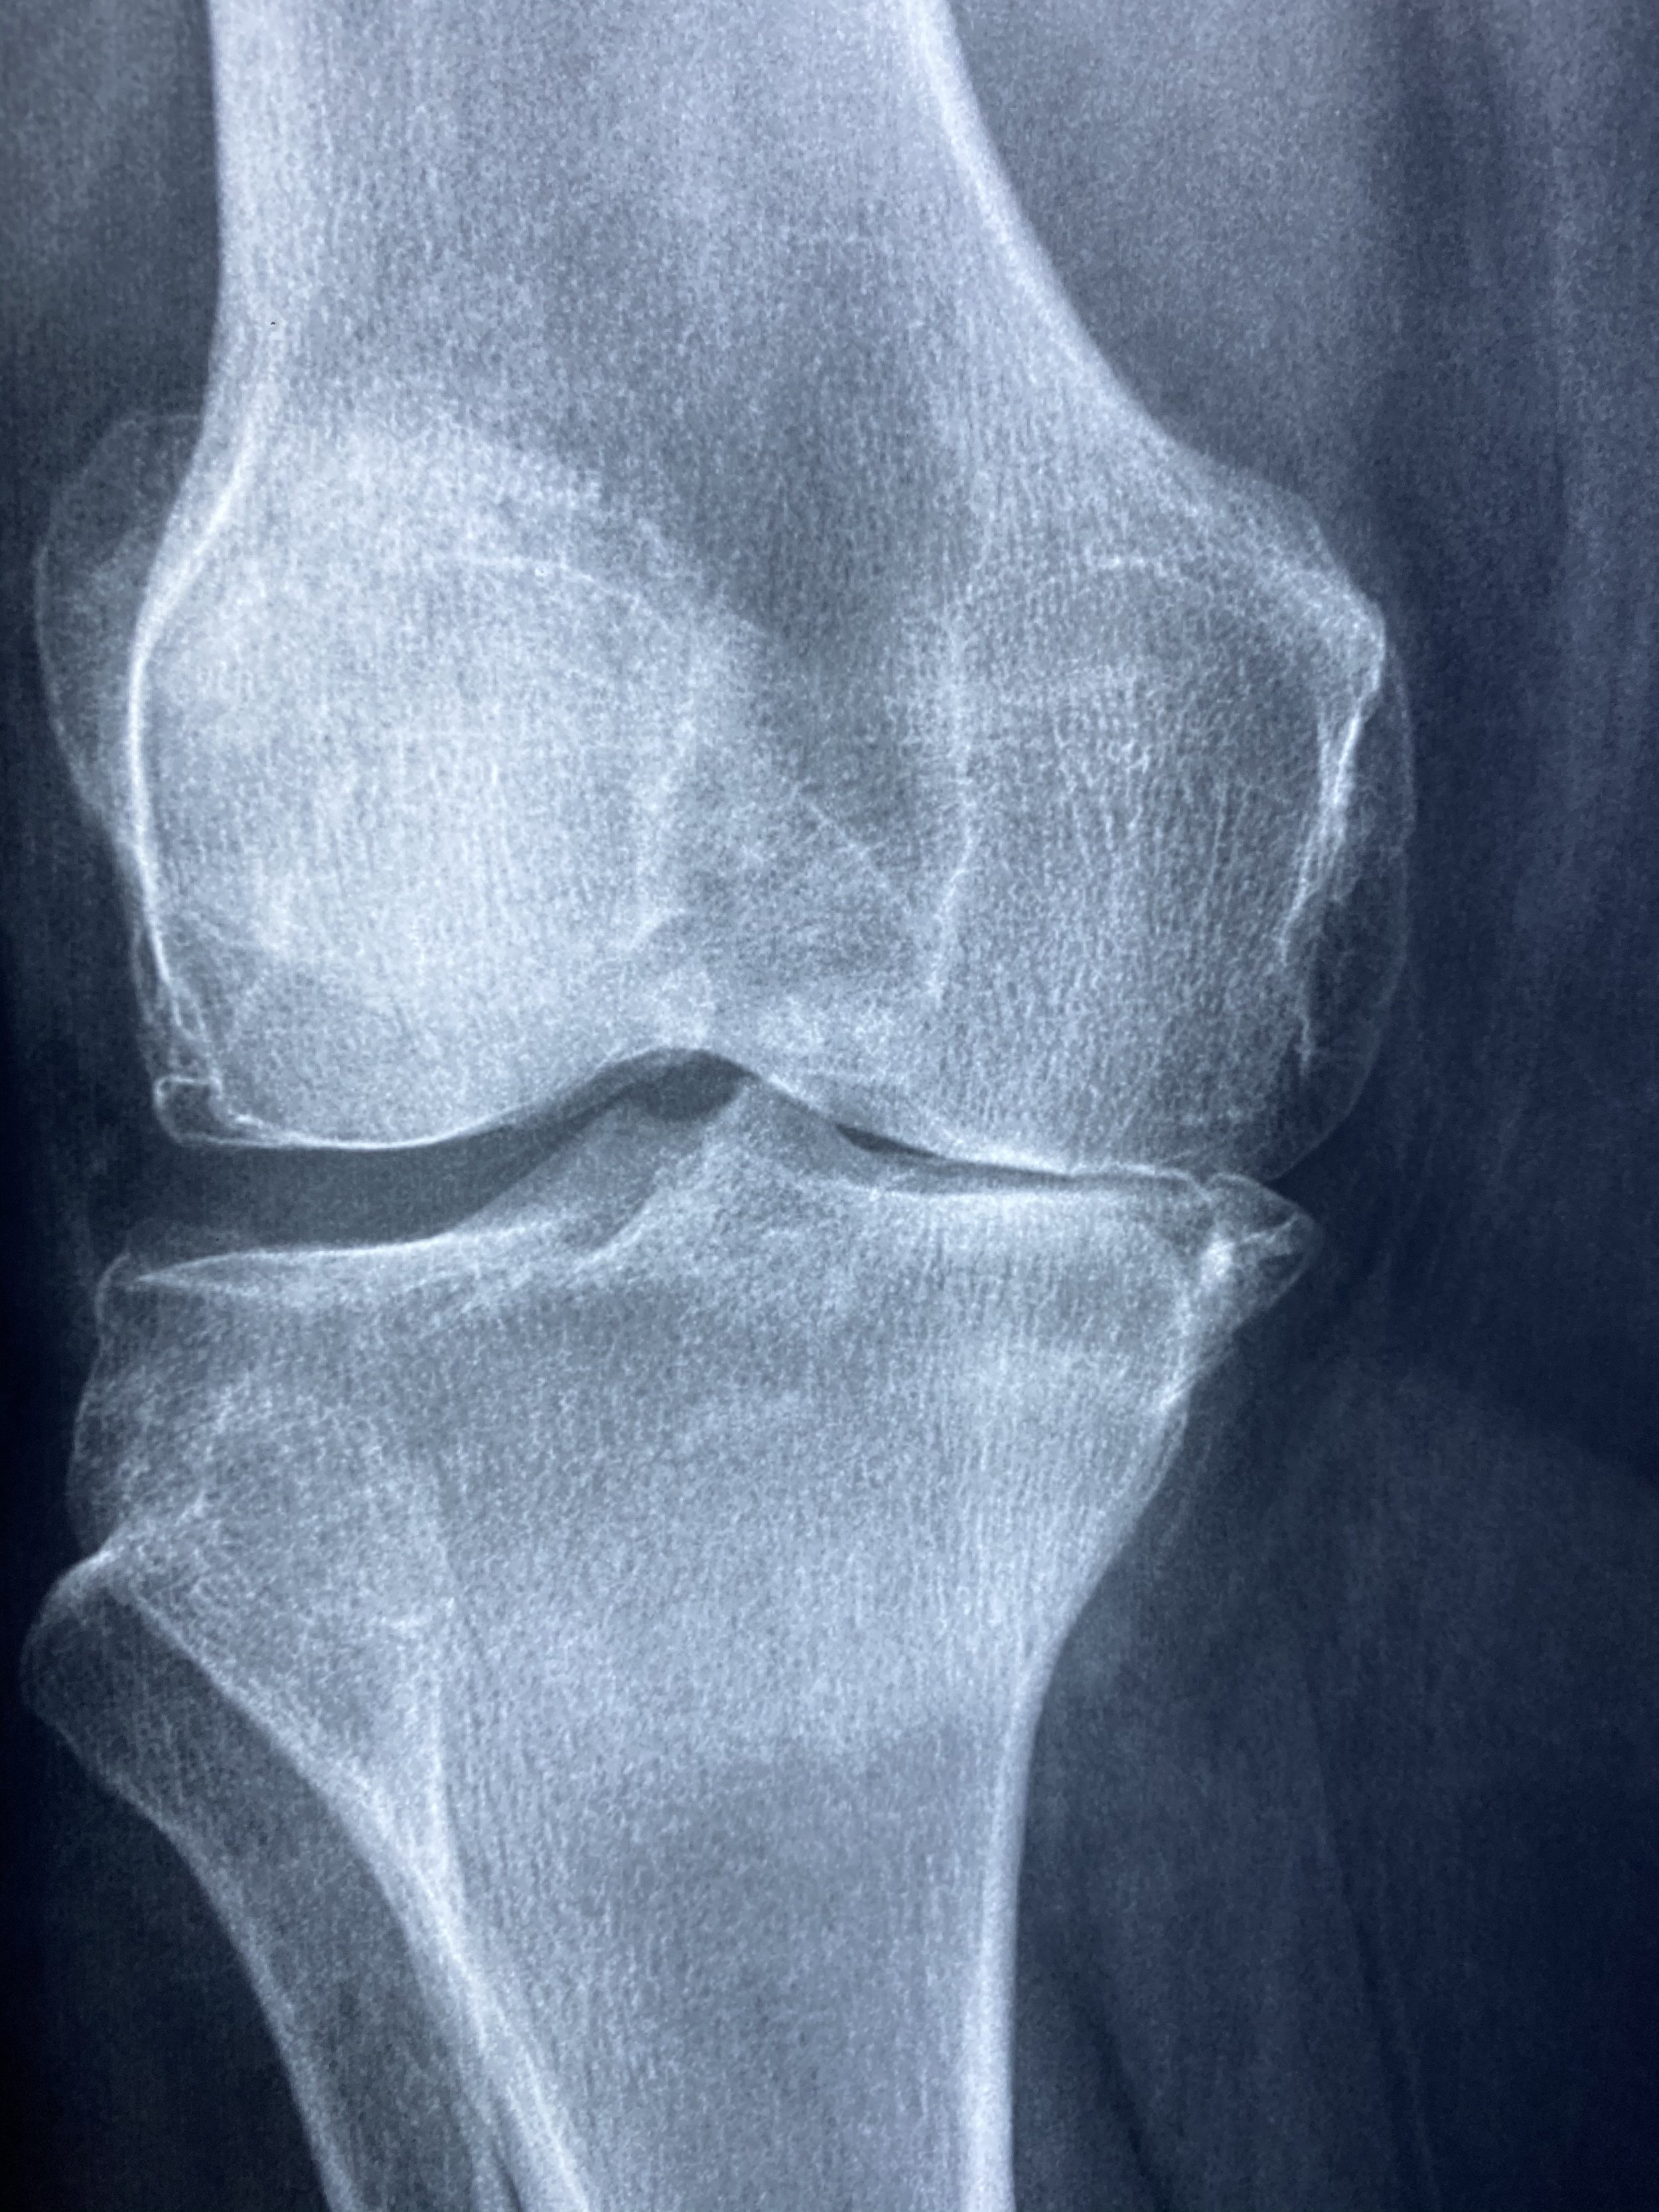

Knee replacement surgery is a major milestone. For many patients, it represents a fresh start—less pain, better movement, and a return to the activities they enjoy.

After a total knee replacement, your body is going through a significant healing process. The joint has been surgically altered, surrounding tissues have been disrupted, and inflammation is part of the normal response.